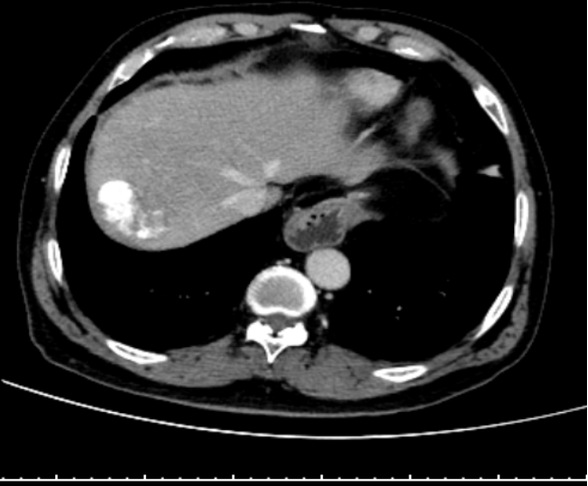

术后3个月复查CT